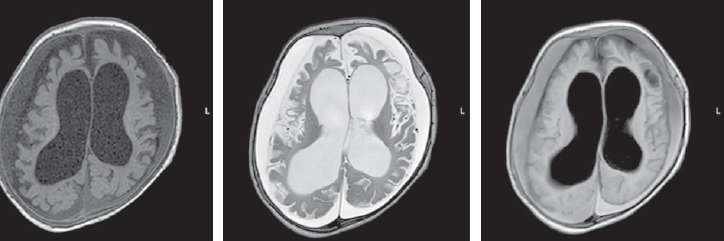

The differential diagnosis of paroxysmal conditions, as well as disorders of muscle tone (hypertension) in the neonatal period and in young children is quite complicated. Various states of the nervous system in newborns are transient and permanent, optimal and suboptimal, normal and pathological. Among them, we can mention non-epileptic paroxysmal states of early childhood. In some cases, non-epileptic paroxysmal states of early childhood is accompanied by motor disorders, manifested by an excessive increase in limb tone in newborns. This pathological condition of muscle tone in the English-language literature is referred to by the term stiffness baby (the syndrome of a “rigid” or “fettered” baby). Neonatal pathological muscle hypertonicity, unlike physiological hypertonicity of muscles of a newborn, is a rather rare condition. The article presents literature data and a description of the clinical observation of a patient with hyperekplexia. Hyperekplexia is a rare paroxysmal movement disorder in young children. The main clinical variants of the disease, methods of diagnosis and correction, the main mutations associated with this condition are considered. The article describes the own clinical observation of an early-age patient with hyperekplexia, its clinical picture, features of paroxysmal states and therapy, neuroimaging data, electroencephalographic phenomena recorded in the patient and genetic testing that confirmed the diagnosis of non-epileptic paroxysmal disorders. The child has a mutation in the ATAD1 gene associated with type 4 Hyperekplexia (618011).